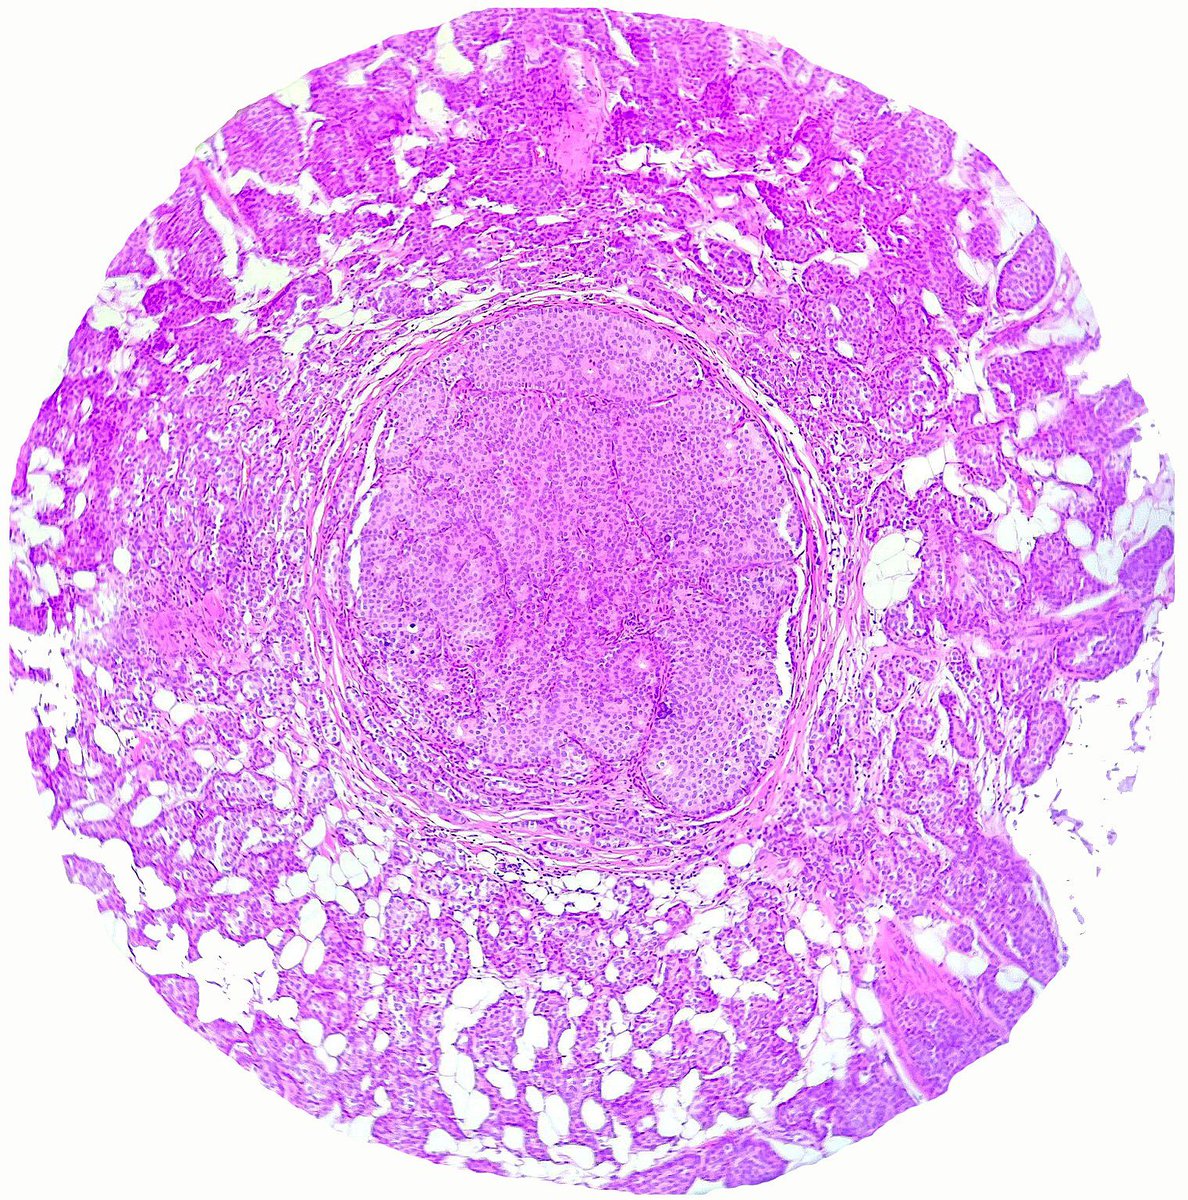

The frozen section